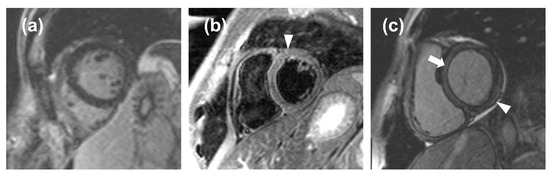

The ROC curve obtained from LGE data from acute-phase patients and controls has a moderate area under the curve, resulting in an optimal threshold of 5% with a high value of sensitivity (87%) but low specificity (48%). Indeed, minimal LGE appears most commonly as a thin, subepicardial line, easily mistaken for adipose tissue, that the software cannot assess with sufficient accuracy, resulting in a falsely negative assessment (Figure 5). This means that quantitative LGE evaluation may be useful for excluding myocarditis in patients testing negative for our threshold, with a negative likelihood ratio of 0.27, which indicates that a negative LGE test determines a reduction of the post-test probability of the disease by 73% as compared to the pre-test probability [21]. Hence, LGE could be used as a quantitative criterion, albeit with certain limitations with regards to its specificity and visual assessment. Our LGE values are lower than those obtained by Ferreira et al. [19] for both acute-phase patients (11%, IQR 5% to 21%) and controls (0%, IQR 0% to 2%), as well as those obtained by Luetkens et al. [22] at the acute phase (15.8 ± 12.0%) and follow-up (7.2 ± 5.9%), whereas our controls LGE values are similar to those reported by Luetkens et al. [22] for controls (4.8 ± 4.4%). Since LGE values for the acute phase and follow-up depend on disease severity, we should highlight that other studies did not exclude patients with a compromised ejection fraction, hence displaying higher values compared to ours, which were derived from patients with mild myocarditis with preserved ejection fraction.

The significant differences in edema observed between the acute phase and follow-up or controls may prove that edema, representing acute inflammation, is higher during the onset and initial stages of myocarditis, while it tends to reduce at follow-up. The ROC curve obtained from edema data of acute-phase patients and controls has a good area under the curve, resulting in an acceptable value of sensitivity (76%) and a high value of specificity (88%). The positive likelihood ratio for (6.33) edema suggests that it could be used to finalize a diagnosis of myocarditis, with a high increase in disease probability when edema tests positive. The negative likelihood ratio for edema (0.27) suggests that it would yield an adequate performance when excluding myocarditis, equal to that of LGE. Therefore, myocardial edema could be used as a quantitative biomarker to be added to visual assessment. Moreover, for quantification of edema, it is notable that the percentage of myocardial volume attributable to edema in controls (median 6.7%) was not significantly different from that of low-risk myocarditis at follow-up (median 7.3%). This finding can be explained by the fact that inflammation is expected to recede in the time intercurrent between the acute phase and follow-up and null at follow-up. The presence of some degree of edema detected in the controls is likely due to signal inhomogeneities or artifacts (Figure 5), which are detected by our semi-automatic software, causing a falsely positive assessment even when the visual assessment by an expert radiologist deems the CMR examination negative for edema. Indeed, as reported by h-Ici et al. [23], the sensitivity and specificity of T2-weighted acquisition for edema assessments are 95% and 78%, respectively. The wish for the highest automatization of LGE and edema quantification for the inclusion of such processes in routine clinical workflows led to the search for new thresholds that could be utilized to deem fully automated LGE or edema quantification positive or negative for myocarditis. In this regard, raising the SD thresholds would not have proven beneficial, as it would have led to a loss of detection of areas where LGE or edema was indeed present.

Figure 5. (a), a false negative case in which the noise masked the late gadolinium enhancement (LGE); (b), a false positive case in which the noise mimicked edema (arrowhead); (c), a false positive case in which an inaccurate inversion time caused a relative hyperintensity of the myocardium (arrow) that mimicked a thin, subepicardial band of LGE (arrowhead).